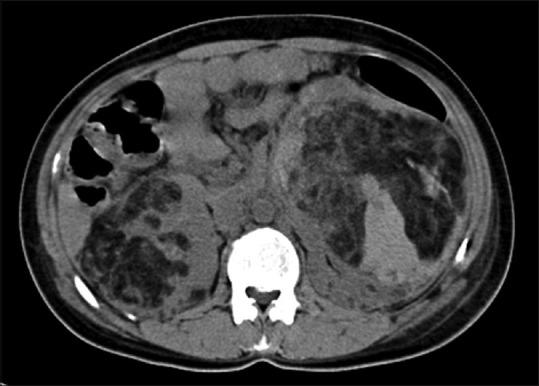

Phakomatoses or Neurocutaneous syndromes are a heterogeneous group of disorders and have variable inheritance pattern. Currently, more than 30 entities are included in this group. These disorders primarily affect the central nervous system; however, skin, viscera, and other connective tissues can also be involved with variable clinical presentation. We will describe and illustrate the various radiological findings of the common entities through the iconography of the cases presented to our department.

phakomatoses或神经皮肤综合征是一组异质性疾病,具有可变的遗传模式。目前,该组包括30多种疾病。这些疾病主要影响中枢神经系统;然而,皮肤、内脏和其他结缔组织也可能受累,临床表现各异。我们将通过提交至我科病例的影像学表现来描述和说明常见疾病的各种放射学表现。